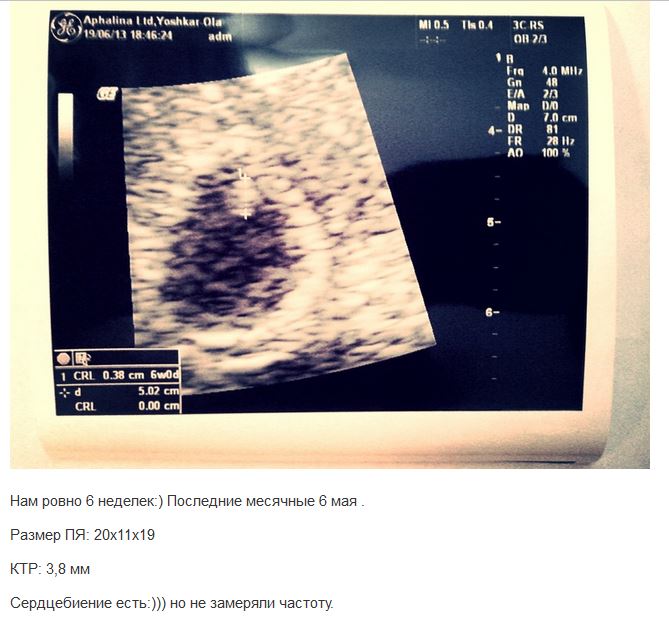

По узи срок 4-5 недель, а не 6+2, сердцебиения нет, а у меня с дочкой в 6+1 ПЯ 20 мм, КТР 3,8 мм, мы надеялись на примерно те же цифры, а тут в 2 раза меньше..

Акушерский срок у нее сегодня вот на этом узи такой же, как у меня вот на этом, даже на день больше: (это мое)

от месячных считали акушерский срок. у меня просто на таком же акушерском сроке, т.е от месячных, на УЗИ в 2 раза было пя больше и ктр.